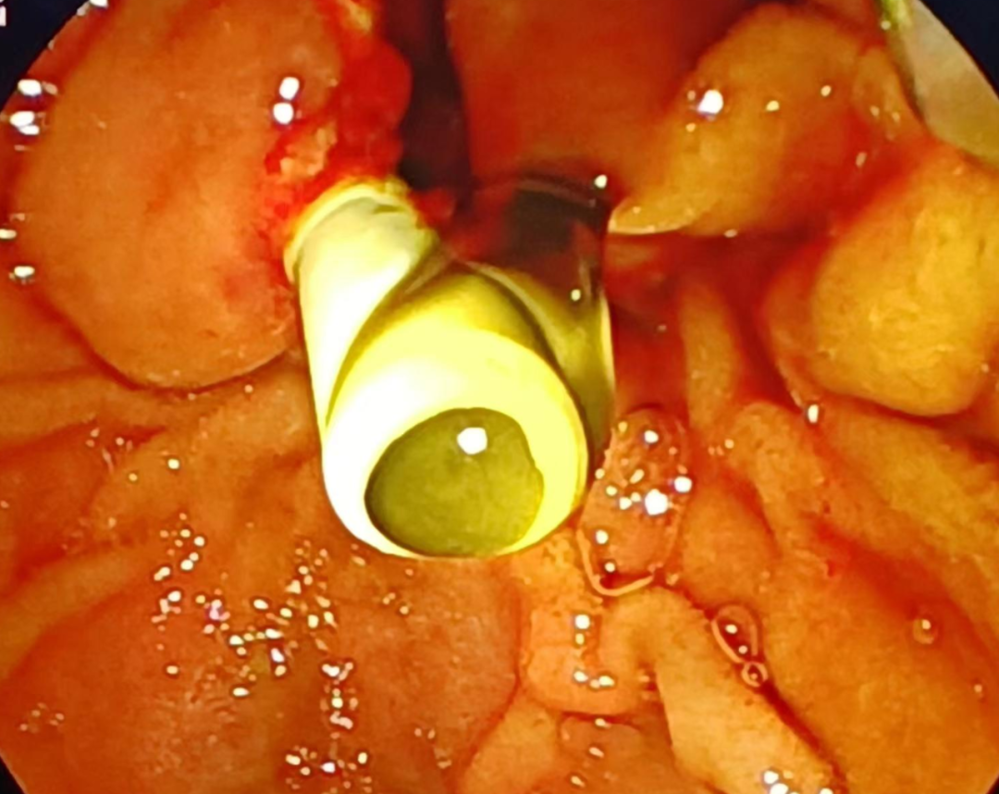

病例資料(liào):患者,周(zhōu)某某,男,51歲。反複尿(niào)黃、眼黃6年餘,6年前在上級醫院診斷為自身免(miǎn)疫(yì)性胰腺炎並膽管狹窄,間斷給予強的鬆治療後症狀反複,2023年11月13日查肝功能(néng)示(shì):直接膽紅素:35.7umol,11月15日行膽(dǎn)道狹(xiá)窄支架置入術(shù),11月20日複查(chá)肝功能示(shì):直接膽紅素:14.11umol,療效明確。

膽道支架置(zhì)入後膽汁流出